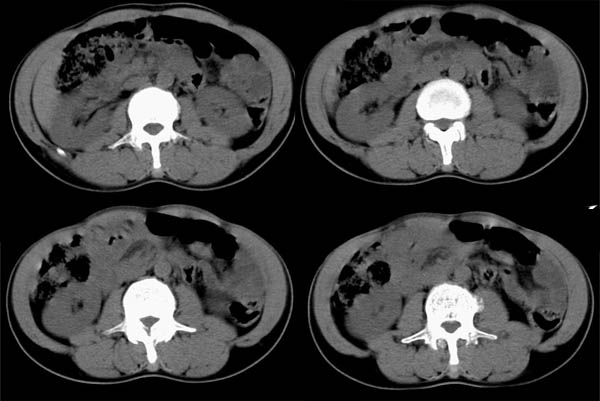

m50y以腹疼、腹胀2小时就诊。腹透肠胀气较明显,余无明显异常。做ct时腹疼已明显缓解;病人否认外伤史,否认血液病变、否认肝炎史。建议第二天做ct增强,病人第二天放弃了增强。脾脏区较高密度影ct值为60hu,正常脾脏ct值为45hu(窗宽:150,窗位:56)。

脾区病变局部2mm重建:

ct表现:脾脏内见较高密度影ct值为60hu,正常脾脏ct值为45hu(窗宽:150,窗位:56)。 边界清晰,周围见略低密度影